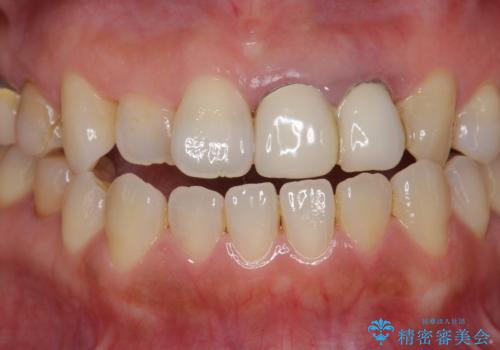

精度、周囲の歯の色調にこだわったオールセラミックブリッジを作製し、しっかりと機能・審美性を改善することができました。